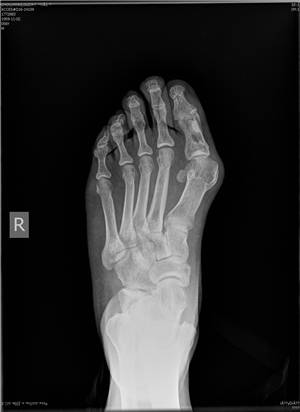

微创矫形方法术前(左)术后(右)X光对比